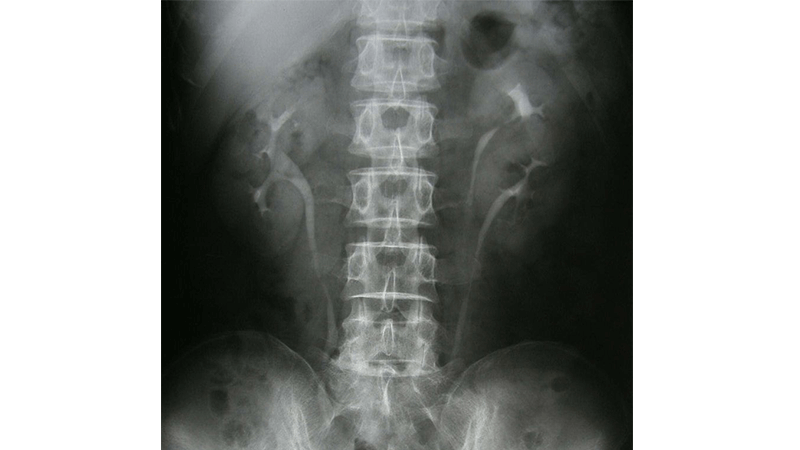

Case Study: Diaper Drama

A case study on the urinary system. Students learn about a baby with recurring urinary tract infections due to a duplicate ureter.